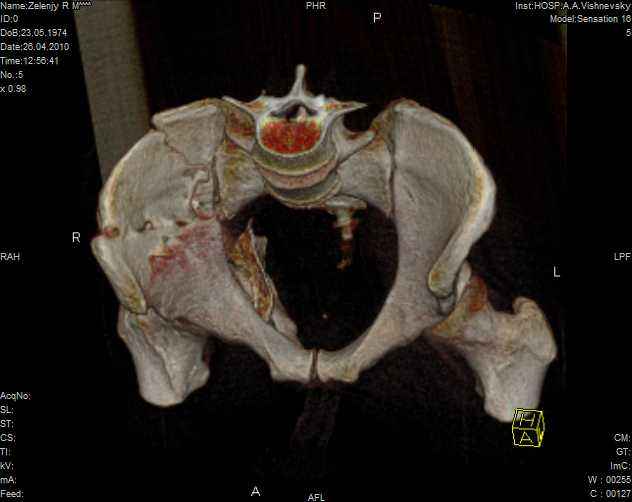

к таковым себя не причисляю, но...обычное дело для нашей страны - выкладывать 3D и не показывать стандартные проекции Judet. Дигност представляет те ракурсы, которые по-его мнению наиболее информативны, более того комп сам достраивает какие-то мелкие повреждения по 3D по своему усмотрению. По данной реконструкции можно предполагать высокий двухколонный перелом с оскольчатыми передней и задней колоннами, оскольчатую высокую переднюю колонну с задним полупоперечником или одно из перечисленных с вовлечение КПС. У меня впечатление за второй вариант, но нужно обследовать нормально - проекции, сканы.

высылаю дополнительно сканы.

Когда перелом не получается отнести к какому либо типу - эффективнее всего описать более детально. В дальнейшем проще бывает сортировать, и что важнее - "руководство к действию" бывает более обоснованным. В данном случае графа клинического диагноза может выглядеть так: Застарелый разрыв правого крестцово-подвздошного сочленения, консолидирующиеся со смещением переломы крыла и тела правой подвздошной кости, обеих колонн и задней гемисферы правой вертлужной впадины. Состояние после остеосинтеза.

Судя по представленным реконструкциям (не очень хорошего качества - много наводок)

мы имеем дело с полупоперечным переломом у которого отломался задний край или его отломали, превратив перелом в полный двухколонный.

По отдельным срезам и тем более по реконструкции трудно судить о сращении крыла и задней колонны с осевым скелетом.

Все выступающие коллеги высказались насчет необходимости стандартных снимков по Judet, потому что для определения тактики лечения переломов вертлужной впадины 3Д снимки малоинформативны.

Из того минимума, что представлено, мне кажется, мы имеем дело с двухколонным переломом вертлужной впадины. Обычно медиальный (центральный) "вывих" головки встречаются в сложных двухколонных переломах со смещением.